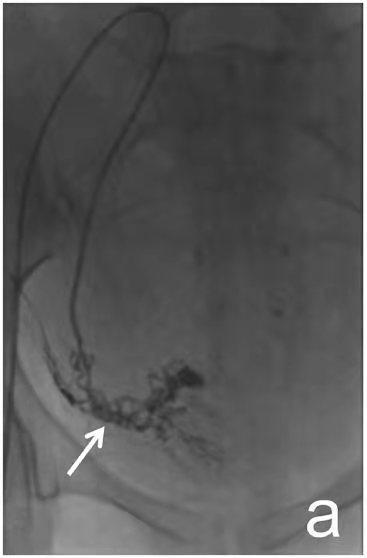

发现左侧上肢血压较右侧低伴活动性头晕2年,超声提示左侧锁骨下动脉狭窄伴随椎动脉反向血流。造影提示左侧锁骨下动脉完全闭塞:

治疗前

介入治疗后,血流顺利通过原闭塞段,左侧上肢血压恢复正常,头晕症状消失。

治疗后